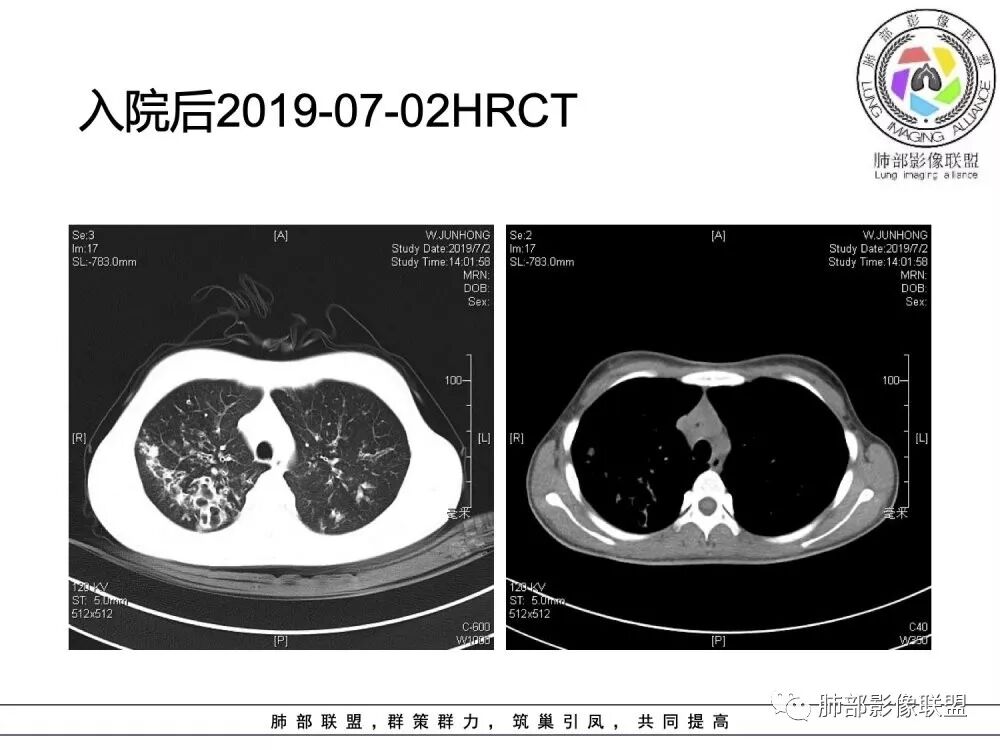

患者青少年女性,以反复咳嗽、咳痰10余年,痰血3年,再发1月余。患者自幼咳嗽、咳痰史,黄白脓痰,曾诊断支气管扩张症,常感乏力,时有腹痛感。有食物药物过敏史。胸CT:病变以双上肺为主,支气管明显扩张,支气管壁可见增厚,可见双轨征,右上肺后段可见囊状改变,并可见片状实变影。诊断考虑:囊性纤维化?鉴别:1 ABPA?2 结核后支气管扩张?

年轻女性,15岁,自幼咳嗽咳痰10余年,痰血三年。两肺呈支扩改变伴小片渗出,双肺上叶为主 。左下见指套状密度偏高影考虑粘液栓,右上部分局限性实变,从病史基本推出诊断,考虑CF。

水晶石头:

病变以双上肺为主,支气管明显扩张,支气管壁可见增厚,可见双轨征 右上肺后段可见囊状改变,并可见片状实变影。患者青少年女性,以反复咳嗽 咳痰10余年,痰血3年,患者自幼咳嗽 咳痰史,黄白脓痰,曾诊断支气管扩张症,考虑:囊性纤维化?

患者15岁,女性,反复咳嗽、咳痰10余年,痰血3年,再发1月余。有腹痛、食物药物过敏史。胸CT:病变双上肺为主,支气管明显扩张,支气管壁可见增厚,双轨征 ,部分可见囊状改变及片状实变影。诊断考虑:CF?鉴别:ABPA;纤毛运动障碍综合征;DBP等

南边老师分析

这个病人15岁,病史10年,一直诊断支扩并感染,但是没提鼻窦病变;广泛支气管扩张,周围有伴随病灶,部分有钙化灶,肺气肿背景,首先是气道来源的病变,表现为:支气管壁增厚、支气管扩张、肺部感染;

(1)支气管壁增厚、支气管扩张

可广泛分布于两肺各叶,尤其是两肺上叶多见。支气管扩张主要是轻、中度柱状支气管扩张。支气管壁增厚既可发生于扩张的支气管,也可发生于非扩张的支气管,常为轻度增厚,管壁内外比较光滑。

(3)支气管黏液栓

由于黏液分泌物潴留在气管内形成,依据黏液存留的支气管走向不同而形态各异,多呈圆形、椭圆形、管状或尖端指向肺门的“V”形或“Y”形高密度阴影,密度均匀,边缘光滑锐利,CT值一般为15±10HU,但存留较久的黏液栓CT值可高达40~80HU,增强扫描无强化。

(5)斑片状阴影

表现为感染性支气管肺炎和亚段肺不张。呈1~3cm大小不等的斑片状高密度影,上肺野常见或上肺野病灶分布较多。